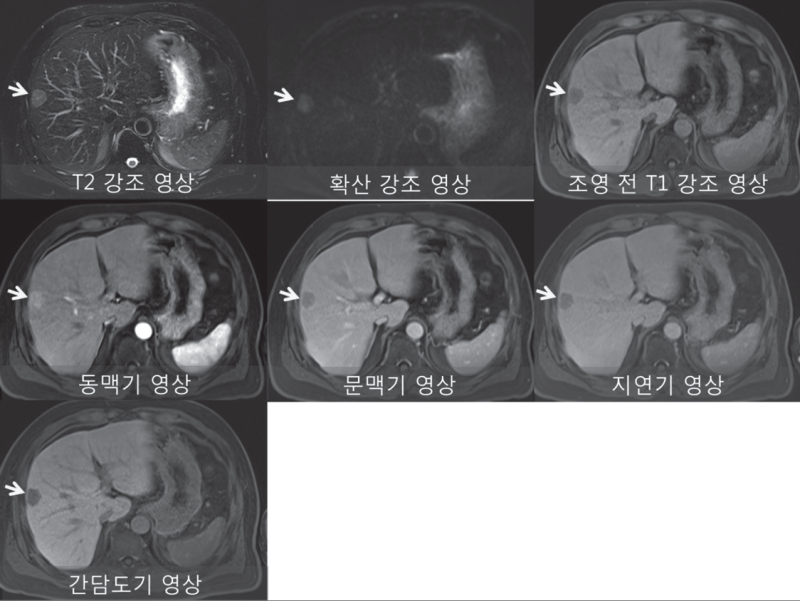

간 석회화와 간경화의 차이점은 무엇입니까? 간경변증은 간세포 섬유조직의 대량 증식, 간 내 소담관의 압박, 다수의 소엽 형성으로 간 전체의 간경변증을 일으키는 것으로 알려져 있다. 실제로 간문맥고혈압, 비장종대 등의 간석회화는 대부분 간에서 석회화점을 형성하는 작은 돌에 의해 발생하며, 담즙정체, 배설불량, 담관벽에 담즙색소 침착 등으로 인해 결석으로 이어지는 경우가 많다. . 작은 석회화된 병변. 간경변증의 예후는 문맥압항진증, 복수, 비장종대를 초래합니다. 그 중 간염 간경화 환자는 점차 원발성 간암으로 발전하여 환자의 건강을 심각하게 위협합니다. 간 석회화는 일반적으로 간의 작은 병변이며 일반적으로 간 기능을 손상시키지 않으며 주기적으로 검토할 수 있습니다. 간 석회화는 비교적 크며 간의 특정 부위에 국한되어 복통, 발열, 간기능 저하 등을 동반하므로 수술적 치료를 고려할 수 있다. 수술 후 절제술은 일반적으로 좋습니다. 간경변증과 간석회화는 병인, 질환의 변화, 인체에 미치는 영향, 예후 등에서 차이가 있음을 알 수 있으며, 간석회화의 예후와 임상적 특징은 간경변증에 비해 양호하다.